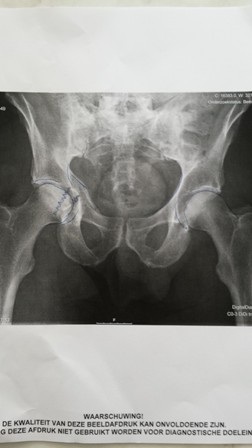

Ik heb een 3 D fotootje bijgevoegd de linker kant is beschadigd (wel mijn rechterbeen) en daar zie dat ten opzichte rechts e.a. in elkaar gedrukt is.

Ik wilde een fiets tochtje maken van ca. 60 km en ben vertrokken richting Ter Aar bij de brug over het Ter Aarkanaal op de T splitsing ben ik met geringe snelheid op op een fietster gereden die plotseling links af wilde slaan c.q wilde keren ik kon niet meer remmen en reed frontaal tegen de mevrouw aan mijn snelheid was ongeveer 10 a 15 per uur maar binnen 2 meter doe je niet veel meer. Ik ben over de kop over haar en haar fiets geslagen en op het asfalt neer gekomen uiterlijk geen enkele beschadiging maar voelde direct dat het in de buurt van mijn heup niet goed zat, gelukkig ben ik niet opgestaan, ziekenauto gebeld en die heeft mij naar Rijnland ziekenhuis gebracht daar constateerden ze op de foto’s gecompliceerde breuk en hebben daar na nog een MRI scan gemaakt hier uit bleek dat het kapot en gebroken was maar dat alle scherven nog op zijn plaats zaten, in tegenstelling wat meestal gebeurt was mijn heupbeen niet gebroken maar heeft met geweld zich door het bekken verplaatst en heeft daar breuken veroorzaakt.

In je bekken liggen je nieren blaas en nog al wat andere vitale onderdelen dat opereren altijd grotere risico met zich meebrengen, men (leids az is zeer goed aangeschreven voor dit soort operaties) heeft besloten omdat alles nog op zijn plaats ligt niet te opereren maar e.a door niet belasten en rust zich zelf te laten genezen.